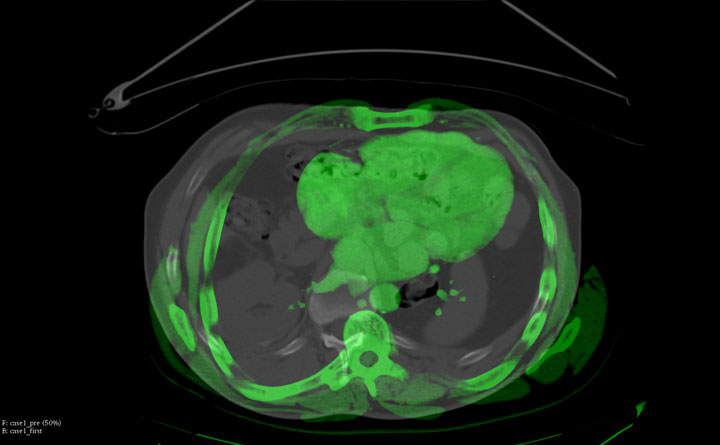

IGTFusion used to guide and confirm accurate needle placement in 3 renal lesions that were not visible on CT during the procedure.

- Registered a supine pre-procedural image to a prone procedural image

- Saved procedure time by eliminating the need to constantly refer back to the pre-procedural image

- Reduced the clinician tedium of estimating the accuracy of needle placement